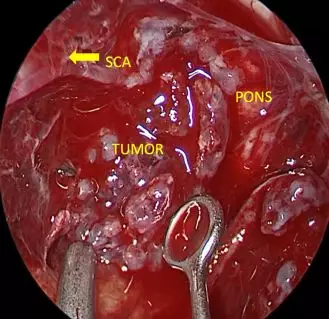

• Debulking Tumor

• After debulking, dissecting tumor margin

• Tumor embedding brainstem appeared